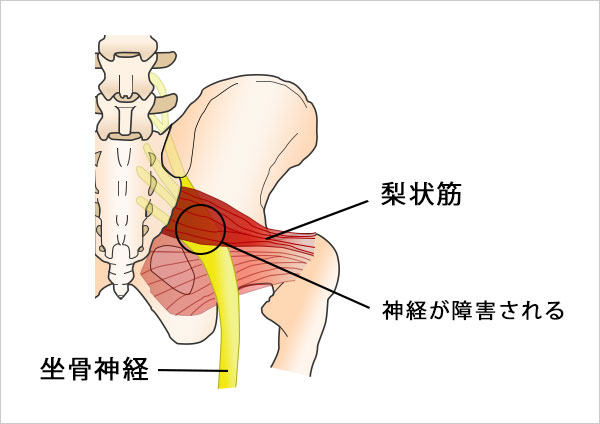

◆ ② 筋肉が原因の場合(梨状筋症候群)

坐骨神経痛の中でも非常に多いのが、

お尻の筋肉(梨状筋)が硬くなることで神経を圧迫するタイプです。

これを「梨状筋症候群(りじょうきんしょうこうぐん)」といいます。

長時間のデスクワークや不良姿勢により、梨状筋に負担がかかり続けると、筋肉が緊張して徐々に固くなります。

固まった梨状筋がすぐそばを通る坐骨神経を圧迫し、

- お尻の奥の痛み

- 太ももの裏のしびれ

- ふくらはぎにかけての違和感

などの症状を引き起こすようになります。

カイロライン三鷹整体院では、この梨状筋症候群に対して、筋肉の深い緊張を緩め、骨盤のバランスを整える専門アプローチを行っています。

筋肉が原因の坐骨神経痛は、適切にケアすると改善が期待できる症状ですので、安心してご相談ください。